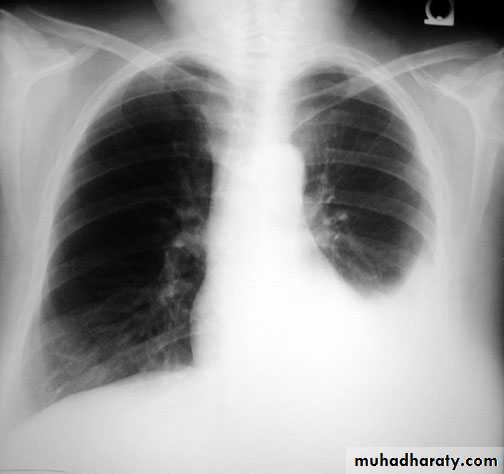

The pleura :

• Pleural effusion : collection of fluid within the pleural space. This can be further divided into Transudate , exudate, according to protein content .Other type of fluid collection within pleural space are

empyema (pyothorax)

chylothorax (lymph in pleural space )

haemothorax

• Chest x-rays are the most commonly used examination to assess for presence of a pleural effusion, however it should be noted that on a routine erect frontal chest x-ray as much as 200-500 ml of fluid is

• required before it becomes evident .

blunting of the costophrenic angle

blunting of the cardiophrenic angle

fluid within the horizontal or oblique fissures

eventually a meniscus will be seen, on frontal films seen laterally and gently sloping medially

with large volume effusions, mediastinal shift occurs away from the effusion

• Lateral films are able to identify a smaller amount of fluid ( about75%)as the costophrenic angles are deepest posteriorly posteriorly

Pleura effusion signs

Obliteration of costo-pherinic anglesMeniscus sign

Lenticular sign